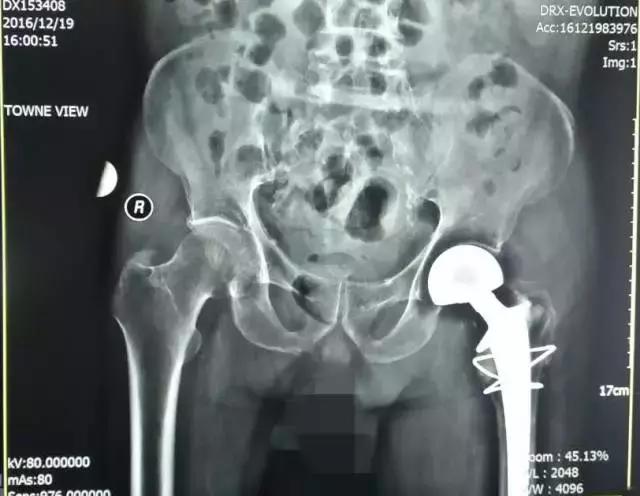

程XX术前X线

程XX术后X线

患者程XX,女,87岁,患者因跌倒致右髋部疼痛,活动受限5天就诊。

入院诊断:1、右侧股骨颈骨折;2、骨质疏松(重度);3、腰椎退行性骨关节病;4、颈椎病;5、双侧膝关节骨关节病;6、左髋关节置换术后;7、白内障;8、消化道溃疡。

诊疗措施:患者因右侧股骨颈骨折伴重度骨质疏松,双膝关节骨性关节病行右侧人工股骨头置换术。术前有重症肺炎,慢性阻塞性肺病,慢性肺源性心脏病等并发症。术中成功置换股骨头,复位后见关节稳定,匹配及活动度良好,术后我科医护人员密切观察患者各项生命体征,积极治疗护理,最终患者恢复了生活自理能力。